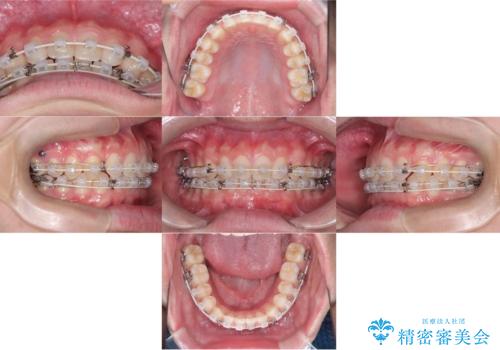

- 主訴:上の歯列の空隙を閉じたい

上顎前歯部に空隙が目立ちました。ワイヤー矯正、インビザライン(マウスピース矯正)どちらの方法でも適用症例と説明し、ワイヤー矯正治療(審美装置)を希望されました。

上顎歯列の空隙を閉じるのと一緒に、ディープバイト気味の被蓋も下顎前歯の圧下を行い改善しました。

矯正治療期間:2年ちょうど